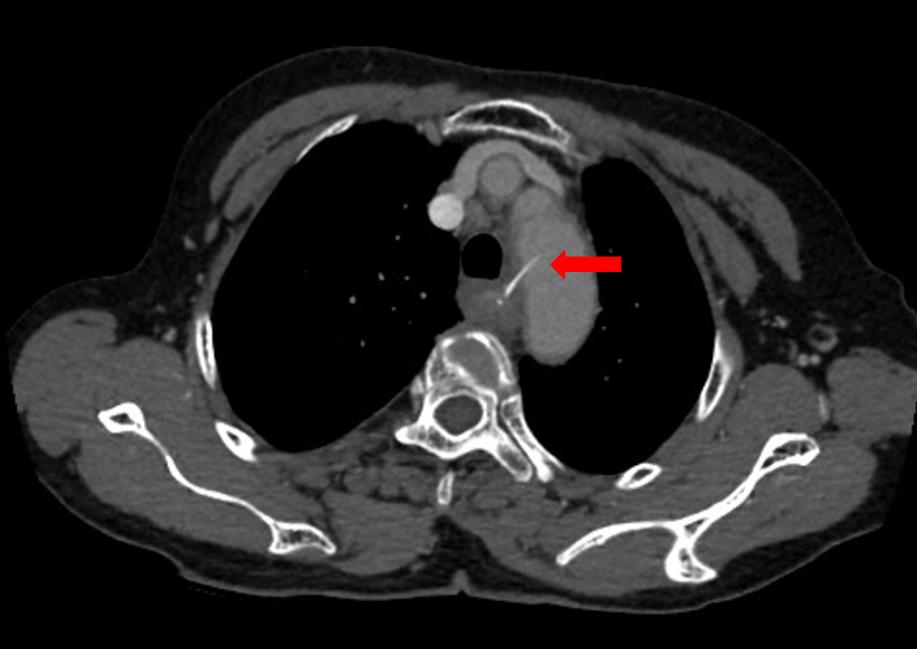

鱼刺卡在这个位置,很棘手,阿婆家附近的医院医疗技术有限,于是,匆匆来到广州医科大学附属第二医院(简称“广医二院”)耳鼻咽喉科就医。为了进一步明确鱼刺的位置,搞清楚它与大血管之间的关系,该科医师立即联系放射科为阿婆做胸部CT平扫+增强检查。值班医师阅片发现,鱼刺已穿破阿婆的食管壁和胸主动脉内侧壁!

CT显示鱼刺穿破阿婆的食管壁和胸主动脉内侧壁。